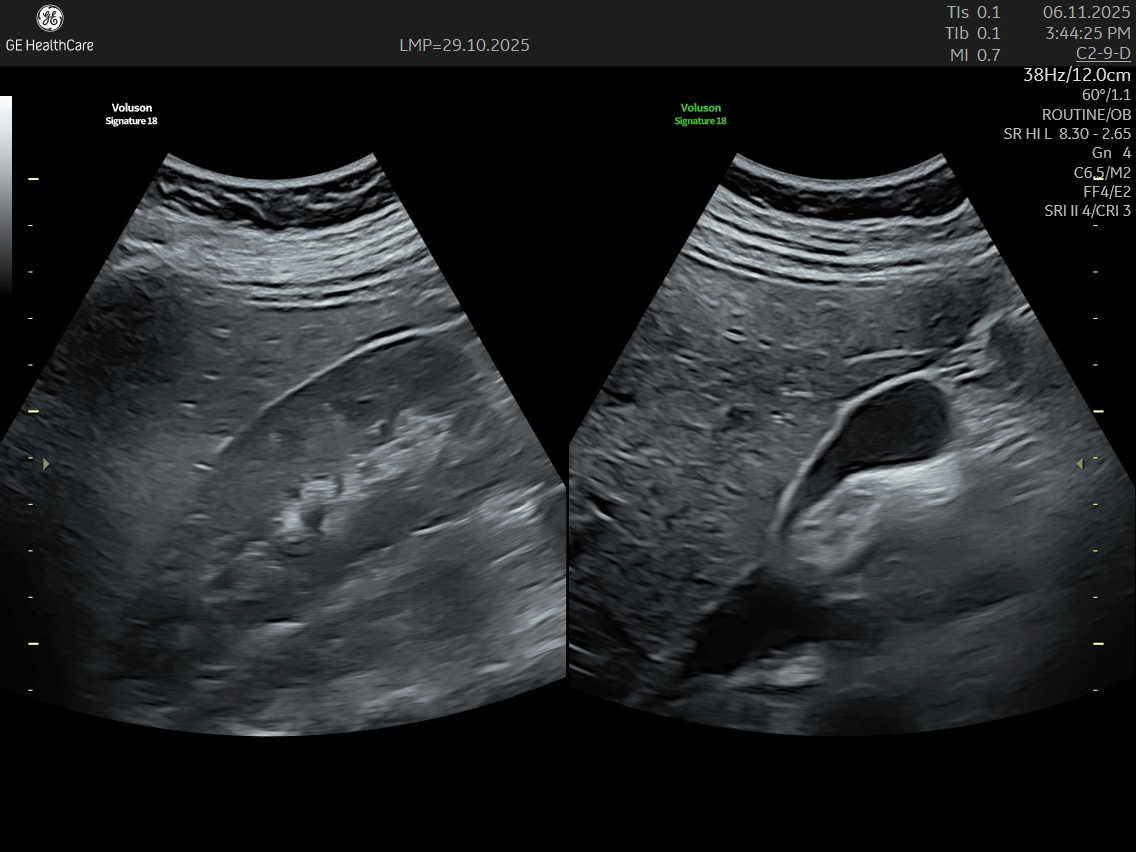

• A transvaginal ultrasound is performed simultaneously to capture detailed images.

IMAGE GALLERY